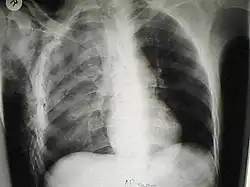

O enfisema pode produzir protuberâncias, como nódulos móveis com ruídos crepitantes a palpação. Em uma radiografia de tórax, o enfisema subcutâneo pode ser visto como estriações radioluzentes (escuras) nas áreas com músculos. O ar nos tecidos subcutâneos pode interferir na radiografia do tórax, potencialmente obscurecendo condições graves, como o pneumotórax. Também pode reduzir a eficácia do ultrassom.[8] Também é visível na tomografia e na ressonância magnética como bolhas escuras.